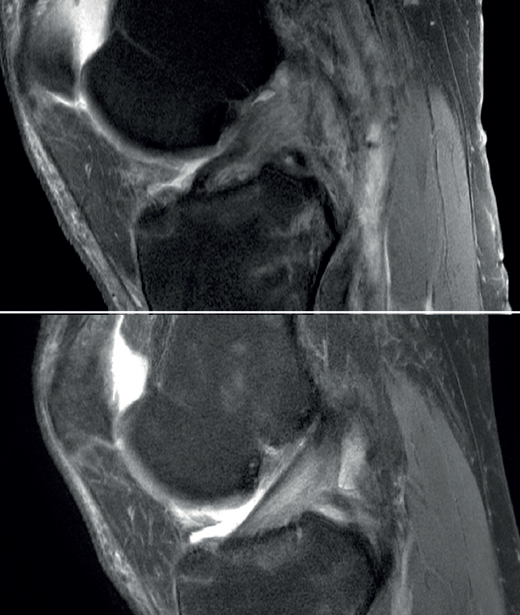

The ACL possesses healing capacity. The fundamental problem may be the formation of a space between the proximal stump and the wall of the lateral condyle in the insertion footprint. This space, occupied by synovial fluid, may inhibit the formation of an organized hematoma and proper healing of the ligament. The problem may be more mechanical than biological(3). The development of specific techniques such as those described above can improve this situation (Figure 11), but does not guarantee healing or the absence of a separating gap between the extremities that would hinder healing(22).